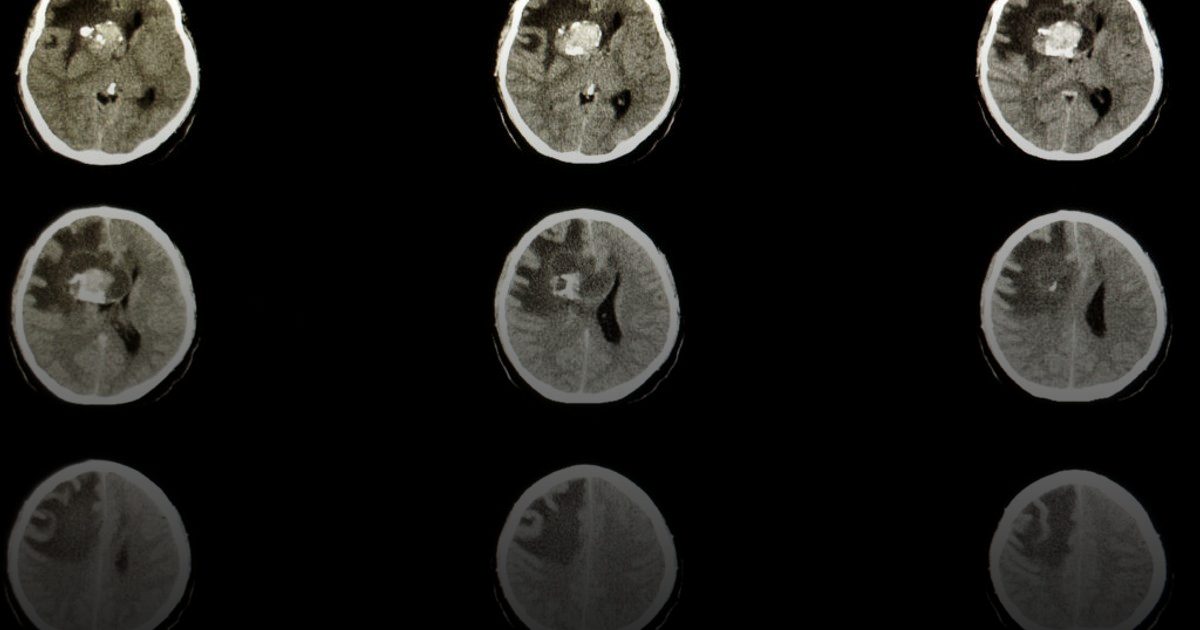

صفقة بمليارات الدولارات لإنقاذ مصابي أورام الدماغ الطفولية

شركة Servier تستحوذ على Day One بعقد بقيمة 2.5 مليار دولار لتعزيز مكافحة سرطان الأطفال.